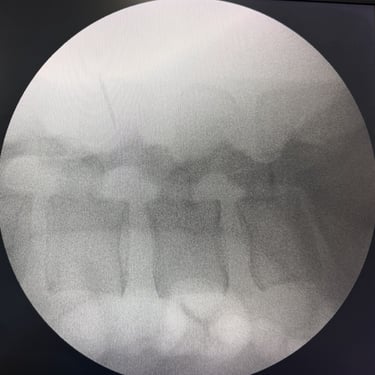

Manejo quirúrgico de la hernia lumbar con inestabilidad: enfoque moderno con FTP y TLIF

La hernia lumbar con inestabilidad vertebral es una patología frecuente que causa dolor lumbar persistente, ciática y limitación funcional, afectando la calidad de vida del paciente. Cuando el tratamiento conservador no logra resultados adecuados, la cirugía se convierte en la mejor opción terapéutica. La fijación transpedicular con tornillos (FTP) junto con la técnica TLIF (Transforaminal Lumbar Interbody Fusion) permite estabilizar la columna, descomprimir las estructuras nerviosas y lograr una adecuada fusión ósea. Este abordaje, especialmente mediante técnicas mínimamente invasivas (MISS), ofrece múltiples beneficios, como menor daño muscular, menor dolor postoperatorio y recuperación más rápida, facilitando el retorno temprano a las actividades cotidianas con mejores resultados clínicos.